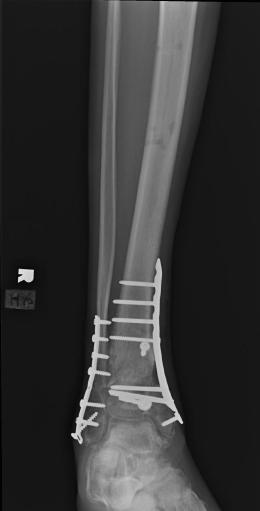

Post-skin graft & bone infuse surgery X-Rays of the left & right ankle

These x-rays were taken four weeks after surgery where grafts of skin were used to cover the open wound on Liam's left ankle. Dr. Gottlieb

infused bone material into the tibia gap of the left ankle. The 3 cm fragment in the left ankle does not appear to have fused or to be

obstructing normal movement so no immediate plans exist to modify the remaining bone fragments. Following these x-rays it is the plan to

remove the right ankle screw that was misplaced by Dr. Keller.